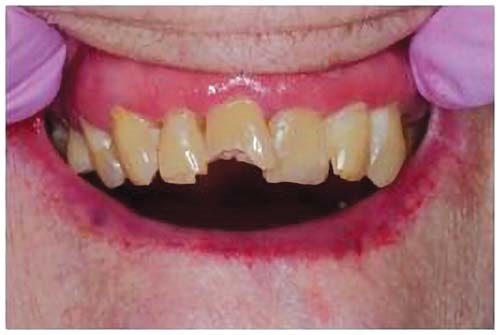

The 94-year-old patient in my chair had a fractured maxillary incisor (Figs. 1 and 2). Although her physical health was good and her basic systems were sound, she suffered from advanced Alzheimer’s disease. I would consider placing a crown for a younger patient, but in this case the expense was not necessary and there was a more practical approach.

At 94, the patient still had a full set of natural teeth, thanks to a lifelong commitment to oral care, but she now suffered from compromised hygiene, xerostomia and a tendency to retain some food in her mouth. A radiograph revealed extensive caries, but the bone was excellent. Fortunately, she is cared for by a loving daughter who wanted her mother’s tooth restored for her comfort and appearance.

Fig. 1: Fractured maxillary incisor of a 94-year-old female patient.